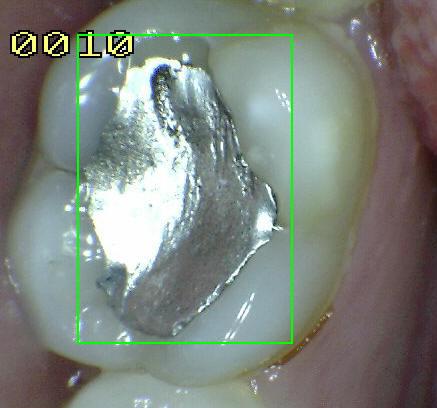

Código 4

(Caries Moderada): Sombra oscura

de dentina subyacente al esmalte intacto con o sin interrupción

localizada del esmalte

- La superficie de los dientes

puede tener características de código 2 y tiene una

sombra de dentina con cambio de color que es visible a

través de una superficie de esmalte aparentemente

intacto o con ruptura localizada en el esmalte pero sin

dentina visible. Este aspecto se ve más fácilmente

cuando el diente está húmedo y es una sombra oscura e

intrínseca que puede ser de color gris, azul, naranja o

café.

- Nota: observar el diente húmedo y luego seco. Esta

lesión debe distinguirse de sombras ocasionadas por

amalgama.